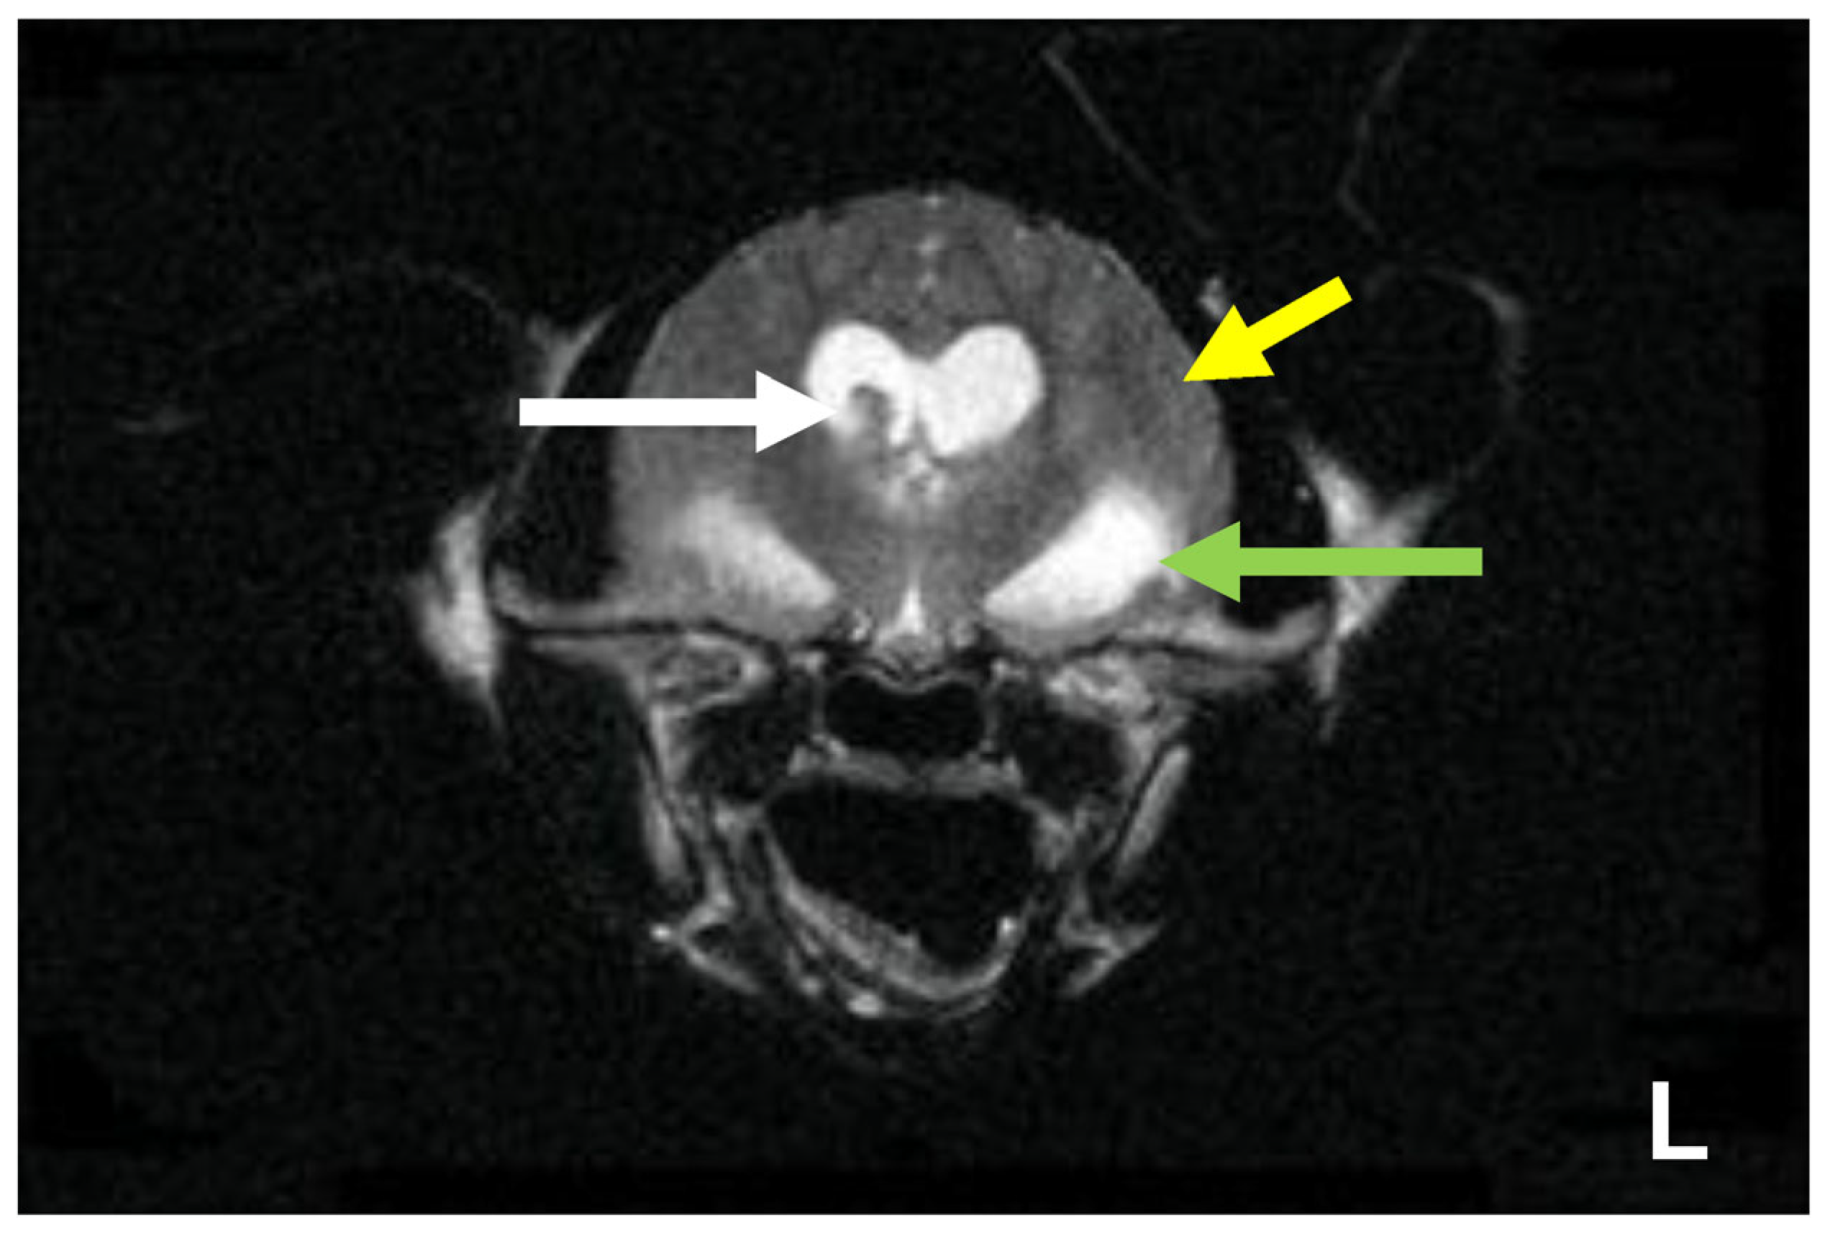

7.4. Diagnostic Imaging in FIP

7.4.1. Routine Imaging: Ultrasonographic and Radiographic Findings

7.4.2. Advanced Imaging of the CNS: MRI and CT

| Summary of Section 7: Diagnosis of FIP; Section 7.4: Diagnostic imaging in FIP: No specific ultrasonographic or radiographic findings exist for FIP. Ultrasonography (in particular) and radiography can show the presence of effusions. Pneumonia due to FIP that is occasionally reported can be associated with radiographic changes. Ultrasonography can reveal abdominal lymphadenomegaly or lymphadenopathy and/or abnormalities of the liver, spleen, intestines and/or kidneys (which can include a medullary rim sign), depending on which organs are affected. Imaging can also be of use to the direct sampling of abnormal tissues, e.g., fine-needle aspirate for cytology examination to reveal non-septic pyogranulomatous inflammation, or ultrasound-guided needle core (e.g., tru-cut) biopsies can be collected and submitted for histopathology. When a cat is showing neurological signs, the imaging of the brain by magnetic resonance imaging, if available, with contrast, can be useful to demonstrate neurological abnormalities (such as obstructive hydrocephalus, syringomyelia, foramen magnum herniation and marked contrast enhancement of the meninges, third ventricle, mesencephalic aqueduct, and brainstem). A description of computerised tomography findings in cats with neurological FIP has not been published, but MRI is likely to be more sensitive in the detection of subtle intraparenchymal lesions. Advanced imaging of the central nervous system is indicated before performing cerebrospinal fluid sampling to assess the potential risk of herniation. |